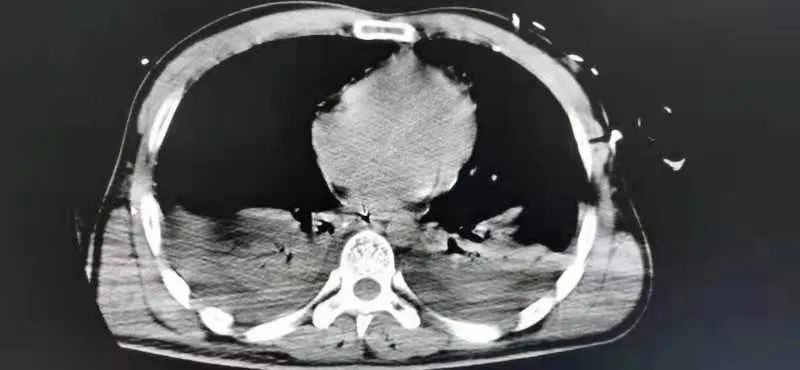

7月一天下午,东院急救中心接诊一名高空坠落的青年男性患者王某,入院时患者神志不清伴全身多处骨折出血,出现失血性休克并严重创伤性凝血病,多项指标均报危急值。东院急救中心立即开辟绿色通道,医护人员第一时间成立抢救小组,进行全方位研判、抢救。通过全身CT检查显示患者脑挫裂伤、双肺多发创伤湿肺、间质水肿、双肺胸腔积液并不张,右上腹游离气体影,考虑胃肠道穿孔,腹盆腔积液积血、腹膜后挫裂伤,胆囊胆汁淤积,右侧多发肋骨骨折,颈、腰锥体压缩性骨折,右侧肘关节、髂骨、股骨、胫骨及骶尾骨多发粉碎性骨折,右侧腰背部、臀部软组织挫裂伤、血肿形成。

经过严密的术前计划及准备,与患者家属协商后,决定先行损伤性控制手术,在气管插管全麻下行肾破裂修补术+胆囊切除术+肝损伤清创修补术+肠造瘘术+右下肢及右上肢清创缝合术。

术后经过严密的监护治疗,患者顺利度过了休克期、ARDS期、感染期。由于患者骨折多发且复杂,为最大限度帮助患者恢复正常生活,创伤中心首席专家周东生教授分四次完成了确定性功能修复手术。患者术后恢复良好,转入康复功能训练期。